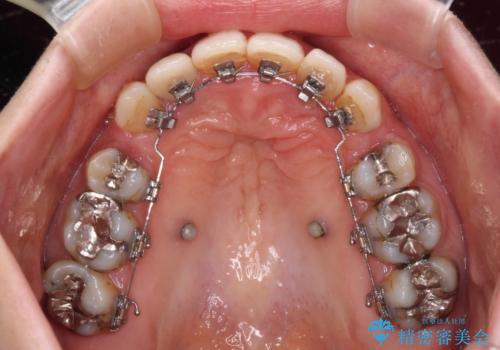

- 矯正装置

- ハーフリンガル

- 上顎前歯が叢生により前方に出ている状態や、全体的なむし歯を気にして来院された患者様です。

口元の突出感を改善するために小臼歯4本を抜歯することとしましたが、左下は大臼歯が欠損していたため、そのスペースを活用し、小臼歯を3本抜歯して治療を行うこととしました。

目立たないハーフリンガル矯正を希望され、裏側装置はどうしても清掃性が低下し、むし歯発生のリスクが高まるため、矯正治療前にしっかりとむし歯治療を行い、矯正治療後にセラミックによる補綴治療を行うこととしました。